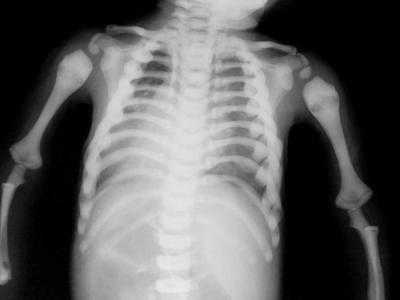

Для диагностики необходимо проведение рентгенологических исследований, выявляющих резкое уплотнение всех костей опорно-двигательного аппарата – основания черепа, трубчатых костей, ребер, позвоночника. Оно выражается в виде абсолютной непрозрачности для рентгеновских лучей, отсутствии лобных пазух и других воздушных полостей, костномозгового канала и выделенного кортикального слоя. На рентгене трубчатых костей могут быть поперечные просветления, напоминающие мраморный рисунок. При внешней не изменённой форме, кости могут иметь утолщения и закругленности на эпифизарных концах и булововидные утолщения метафизов костей.

Для уточнения диагноза назначают рентгенологическое исследование плоских и трубчатых костей: рентгенографию черепа, рентгенографию позвоночника, рентгенографию бедер и т. д. На всех снимках выявляется резкое уплотнение костной ткани. Эпифизарные отделы трубчатых костей закруглены и утолщены, в области метафизов определяются булавовидные утолщения. Все кости непрозрачны для рентгеновского излучения, кортикальный слой и костномозговой канал не просматриваются. Иногда в метафизарных областях обнаруживаются участки поперечного просветления.

Для диагностики врожденного семейного остеопетроза применяют рентгенологические методики, общие анализы крови, молекулярно-генетические исследования, изучение наследственного анамнеза больного. На рентгенограммах выявляют общее уплотнение костной ткани (диффузный остеосклероз), выраженность которого больше при аутосомно-рецессивных вариантах заболевания. В некоторых элементах скелета (фаланги пальцев, подвздошные кости, позвонки) остеопетроз имеет очаговый характер, создавая характерную рентгенологическую картину, известную как «кость в кости». В длинных трубчатых костях изменяется форма метафизов и размеры костномозгового канала – от незначительного уменьшения при доброкачественном типе врожденного семейного остеопетроза до практически полного исчезновения при рецессивном. На рентгенограммах также могут выявляться признаки гидроцефалии, искривления позвоночника, у взрослых – следы многочисленных заживших переломов.

На рентгеновских снимках выявляется генерализованный остеосклероз. Кости имеют гомогенную структуру, костномозговой канал отсутствует. Метафизы длинных трубчатых костей булавовидно расширены. На рентгенограммах черепа определяется склероз и уменьшение пневматизации синусов. Поздний остеопетроз наследуется по аутосомно-рецессивному типу и проявляется теми же симптомами, однако, заболевание манифестирует в возрасте 10 лет или позже и отличается меньшей распространенностью остеосклероза.